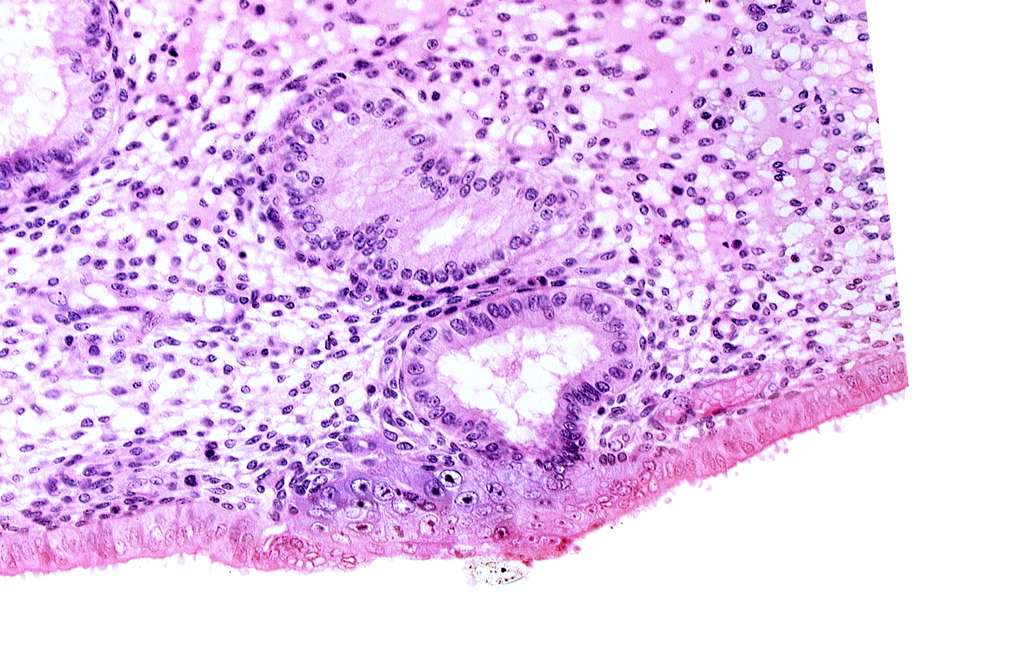

Carnegie Embryo #8020 | Location: 06-05-02

Keywords: disrupted endometrial epithelium, edematous endometrial stroma (decidua), endometrial gland, solid syncytiotrophoblast, syncytiotrophoblast / decidua interface

Source: The Virtual Human Embryo.